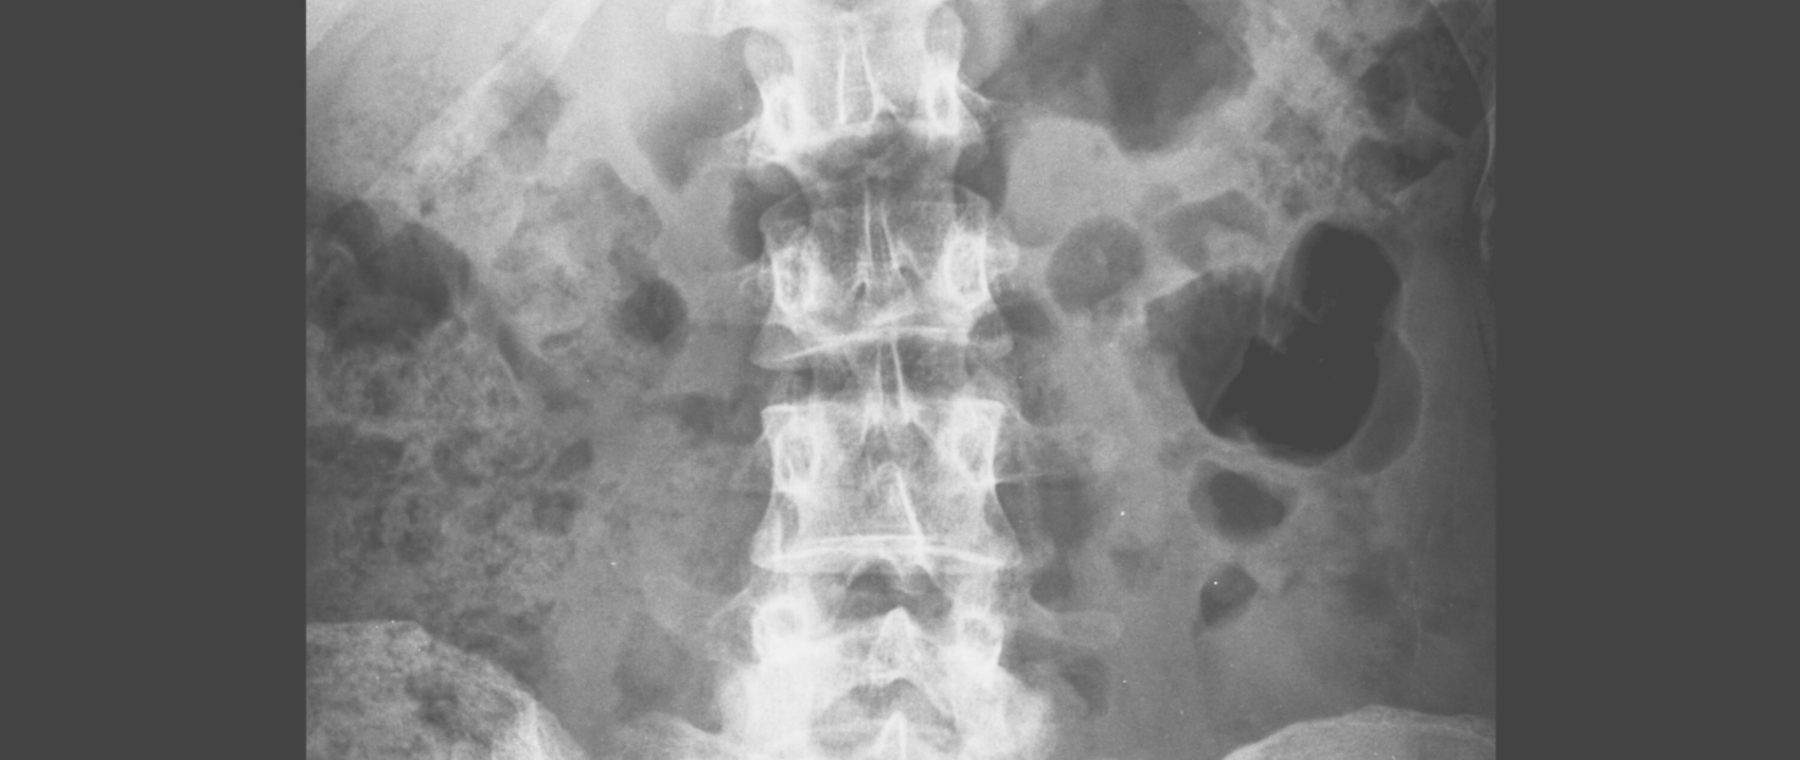

PKD is a genetic kidney disease that causes cysts to grow in the kidneys over time. There are two main types: